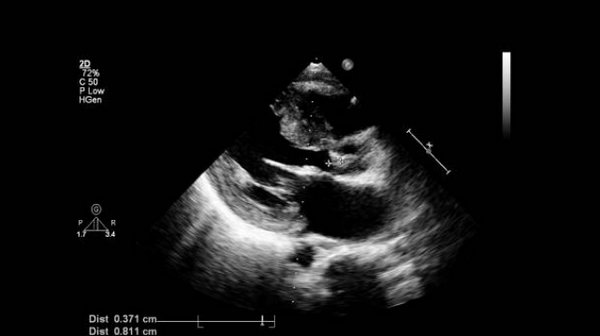

ЭхоКГ можно использовать для исследования аорты. У взрослых первые несколько сантиметров аорты можно увидеть как тонкую, яркую трубчатую эхоструктуру на трансторакальной эхокардиографии на парастернальной длинной оси и в апикальной 5-камерной проекции. ЭхоКГ (в M-режиме или 2-D) можно использовать для измерения размеров корня аорты и восходящей аорты в 4 точках во время конечной диастолы (кроме кольца аорты, которое измеряется в середине систолы): фиброзное кольцо АК, синусы Вальсальвы, синотубулярный переход и восходящая аорты. Перед операцией на аортальном клапане необходимы подробные знания и количественная оценка морфологии корня аорты и аортального клапана. Эти параметры также важны с увеличением использования процедур транскатетерной имплантации / замены AК (TAVI / TAVR).Максимальные диаметры указаны в таблице.

Аортальная недостаточность (АН) — это рефлюкс крови из аорты в ЛЖ во время диастолы. Все методы эхокардиографии полезны в диагностике и оценке аортальной недостаточности. Особенно полезны доплеровские и цветной допплеровский режим. М-режим и двумерная ЭхоКГ не могут напрямую диагностировать АН, но могут указывать на основные причины (например, расширенный корень аорты, двустворчатый аортальный клапан) и помогать в оценке эффектов АН (например, дилатация ЛЖ).

M-режим и 2-D ЭхоКГ показывают дилатацию ЛЖ с тяжелой АН. Прогрессирующая дилатация с симптомами или конечный систолический диаметр левого желудочка (КДРЛЖ) более 5,5 см являются показаниями к хирургическому вмешательству. Допплерография достаточно хорошо показывает тяжелую АН, но не очень хорошо различает легкую и умеренную аортальную регургитацию.

Используя импульсно-волновой допплерографию, контрольный объем можно разместить в различных положениях внутри полости ЛЖ, чтобы дать полуколичественное представление о степени тяжести, наблюдая, как далеко в полость ЛЖ проникает струя AР. В целом, легкая АН остается в области АК, умеренная АН остается между выходным трактом левого желудочка (ВТЛЖ) и уровнем МК выше уровня папиллярных мышц, а тяжелая АН распространяется до верхушки ЛЖ. Это дает только грубое и приближенное представление о тяжести регургитации, так как например узкая струя легкой АН может распространяться глубоко в полость ЛЖ, в то время как сильная широкая струя АН может иметь эксцентрический угол и не распространяться далеко в ЛЖ. Используя цветовое отображение потока, ширина струи регургитации непосредственно под AК указывает на серьезность. Это относится к области плохого закрытия клапанов (регургитирующего отверстия). Ширина струи> 60% ширины аорты на уровне створки обычно серьезна. Можно сделать стоп-кадр AР и использовать планиметрию для оценки площади поперечного сечения струи. Длина струи АН в полость ЛЖ на апикальной 5-камерной проекции также может указывать на тяжесть (более длинная струя - более тяжелая АН).